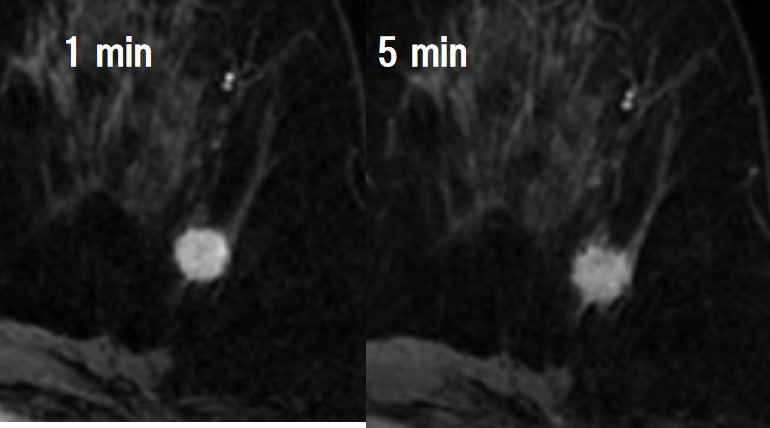

円形・境界不明瞭で、内部不均一なfast-washout pattern*を呈する

造影で内部均一、漸増型*